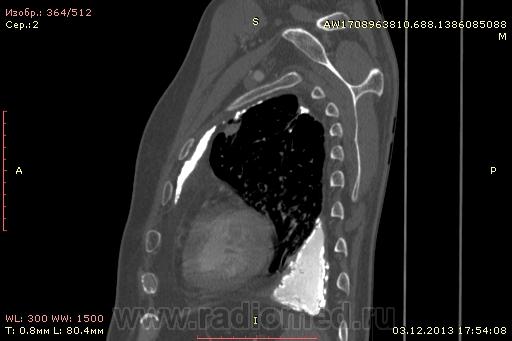

Доброго времени суток уважаемые форумчани! :)Провели исследование КТ грудной клетки с контрастированием, для выявления аневризмы грудного отдела аорты. В результате увидели это:

??? Аневризму честно не вижу (мало опыта в определении аневризм). Тромбоз в бассейне верхней полой вены. В левом легком обызвествленные плевральные шварты? как исход осумкованного плеврита неизвестной давности?

Ребята, вы что, какая жидкость? Чистая известь, посмотрите в костном окне. Отставить натив (в данном случае, хотя для аневризм он обычно нужен). Отставить тромбоз верхней полой вены (потоковые артефакты, не дело вены в артериальную фазу оценивать). Отставить аневризму  аорты, поперчник восходящего отдела на уровне легочного ствола 42мм. А вот легочная гипертензия, здравствуй: поперечник легочного ствола - 37мм, ПЛА - 25мм, ЛЛА - 25мм, НАо - 25-34мм.

Нет ТЭЛА. Фиброторакс слева.

Для справки: холестериновые камни имеют плотность менее 100 ед.Н. Имеющаяся хренотень в левом гемитораксе имеет плотность больше костной, до 1500 ед.Н. Вопрос: какая химико-физико-биологическая реакция может способствовать превращению мягинькаво холестерина в термоядерную плевральную лепёшку?)